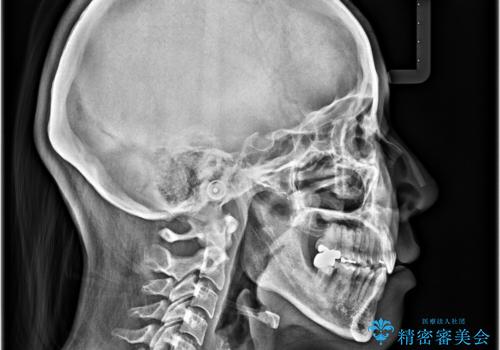

前方に飛び出した前歯 ワイヤー装置での抜歯矯正

通常であれば上下左右の第一小臼歯4本を抜歯して口元の突出感を改善しますが、下顎前歯が1本欠損しており、上下の歯の数がアンバランスであるため、4本抜歯するかどうか悩むところでした。

上顎前歯はやや小さめで、下顎前歯はやや大きめであったため、上下左右4本を抜歯しても左右奥歯の咬み合わせは理想に近い状態を達成できると判断し、上下左右の第一小臼歯4本を抜歯し、ワイヤー装置にて矯正治療を行うこととしました。

当初目論見通り、左右奥歯の咬み合わせはしっかりとさせることができました。

下唇に跡がつくほど飛び出していた上顎前歯も引っ込み、満足のいく仕上がりとなりました。